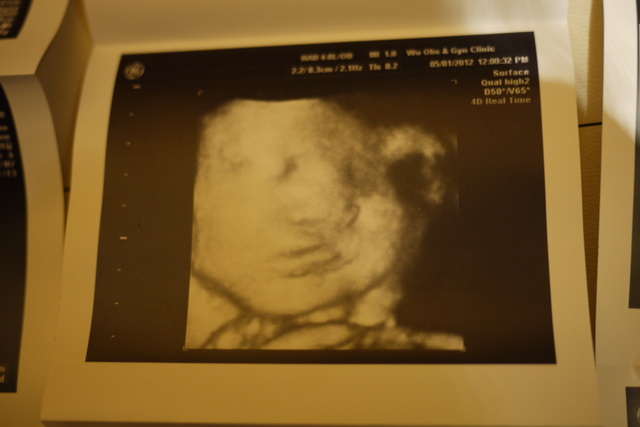

第24 ( 第六月 )

五官越越清楚......手放在旁.....睡得很香甜~~~~

第26 ( 第七月 )

始有肉~~~~ 多了!!!!!

差不多要有1000公克~~~~~